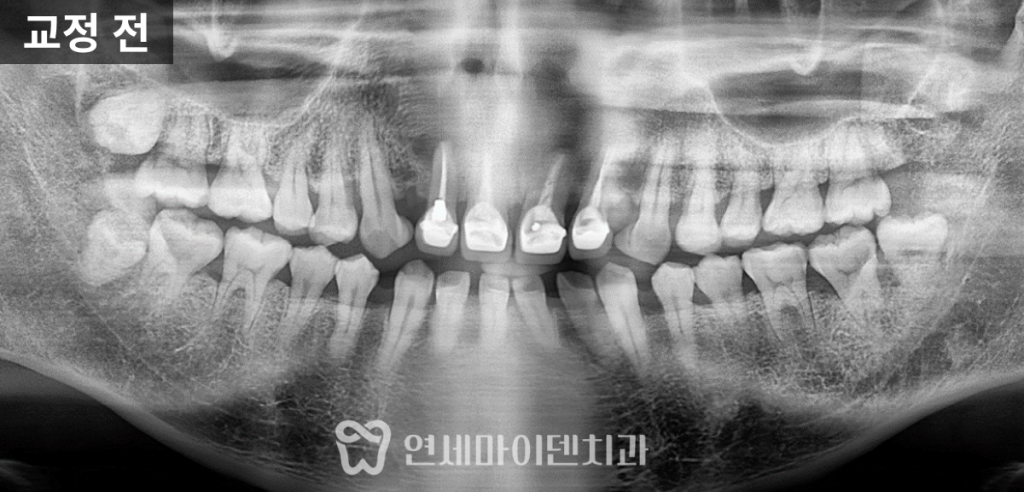

이 환자분은 앞니 사이 공간이 넓다는 주소로 내원하셨습니다.

위아래 앞니는 모두 벌어져 있었고,

앞니 네 개는 이미 보철이 되어 있었습니다.

과거 치과치료 시 공간을 메우기 위해

레진을 채운 흔적도 확인되었습니다.

특히 오른쪽 위 두 번째 앞니는

치근단 부위에 염증이 발생하여 발치가 불가피한 상태였습니다.